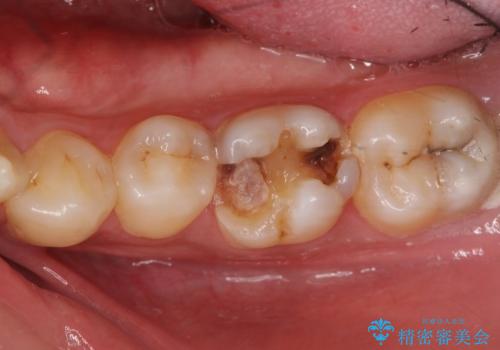

- 右下の奥歯が割れてしまい、抜歯を行いました。

左下に関しては、経過観察を行い、歯が割れたりした場合にインプラントを考えることになりました。